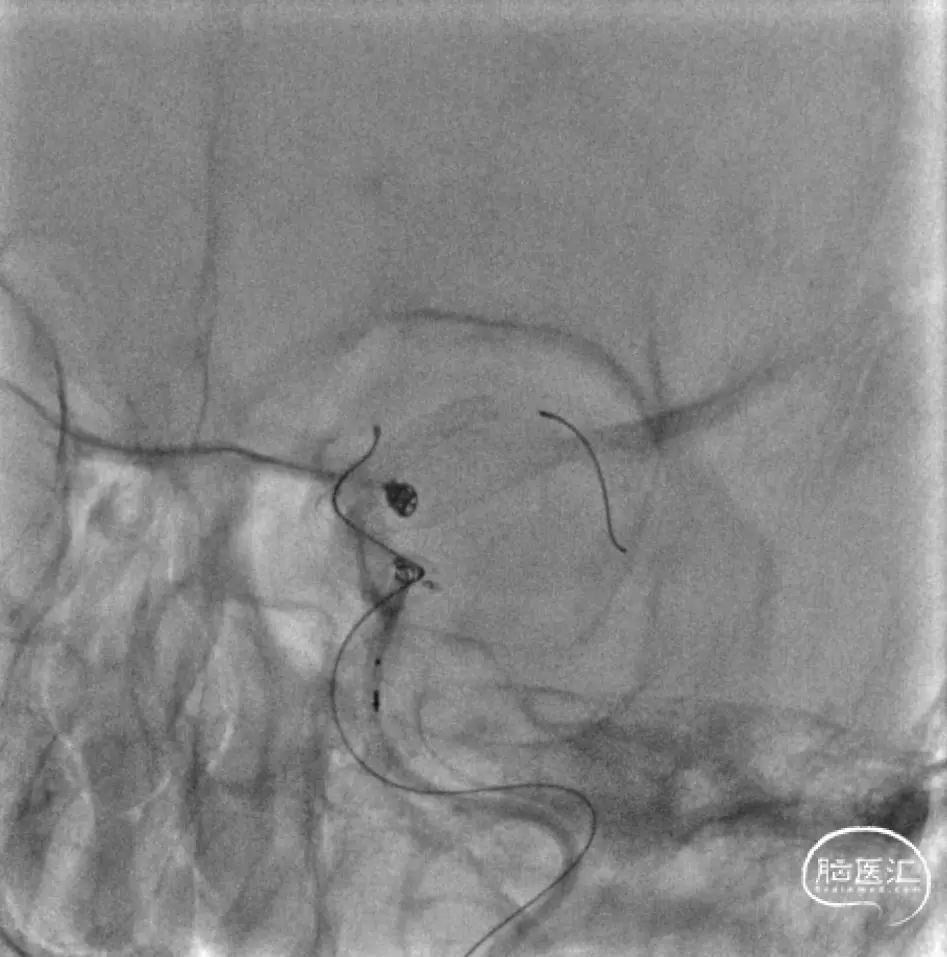

半释放PED,将3mm*4cm弹簧圈完全盘入下方动脉瘤,后将2mm*4cm收尾圈盘入,见致密栓塞,瘤颈封闭满意。后经另一根微导管,将两枚3mm*8cm成篮圈、一枚3mm*6cm成篮圈、两枚2mm*4cm Avenir系列收尾圈,盘入上方动脉瘤,可见瘤颈封闭满意、形成锚定。撤出微导管,微导丝按摩PED。

观察PED贴壁及打开满意。

正侧位及旋转造影见动脉瘤栓塞满意。